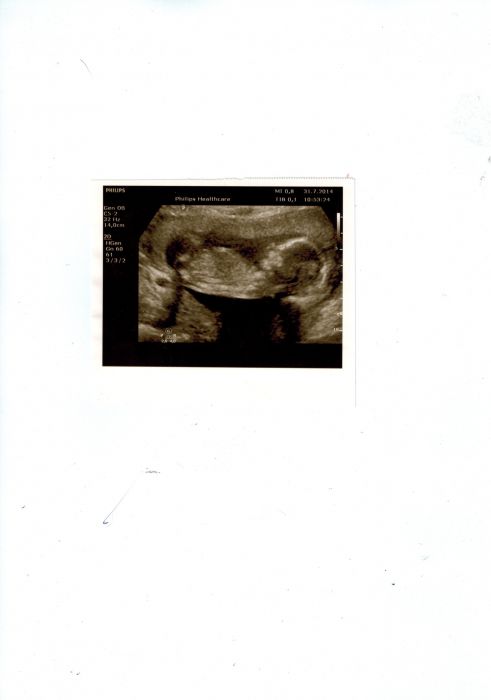

Ahoj holky, Tak potvrzuji další čárku k holkám :-) Dneska ta potvůrka parádně roztáhla nohy :-) jsme 18+4 a měří od hlavy k zadku 14 cm ;-) Zatím je vše v pořádku :-) Přeji všem krásný den!